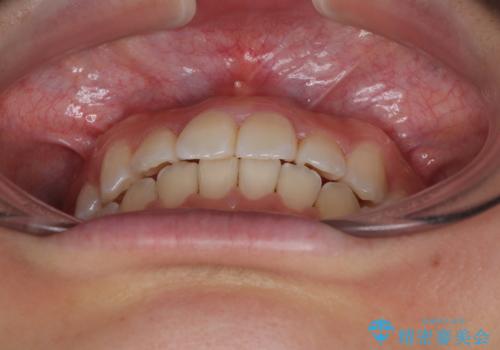

前歯のクロスバイト 裏側に隠れた歯をワイヤー装置で短期間治療

想定通り、1年強で綺麗に仕上げることができました。